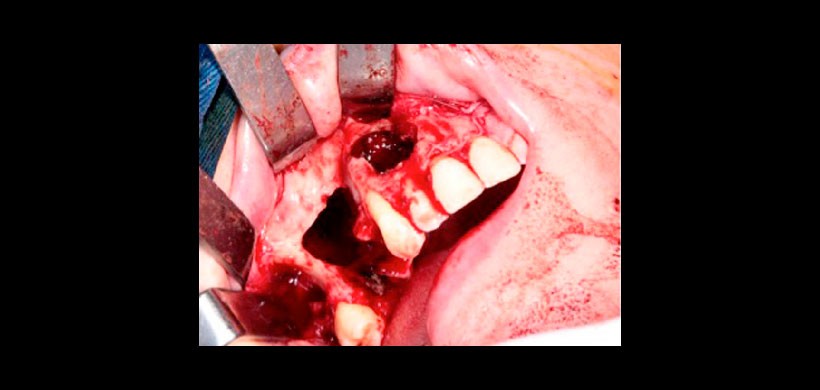

Figura 8: Cirugía de enucleación de la lesión con exodoncia de las piezas 1.6 y 1.5.